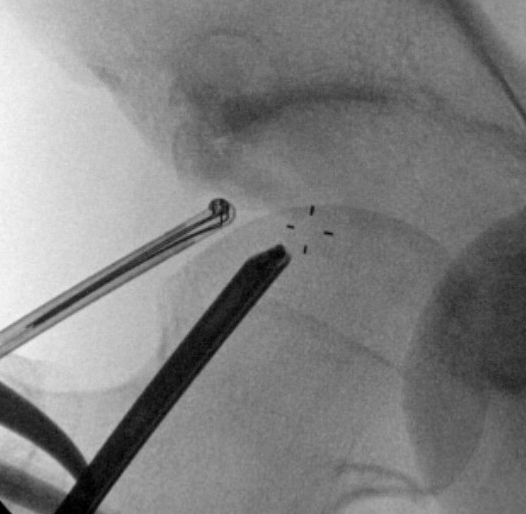

Posterolateral portal